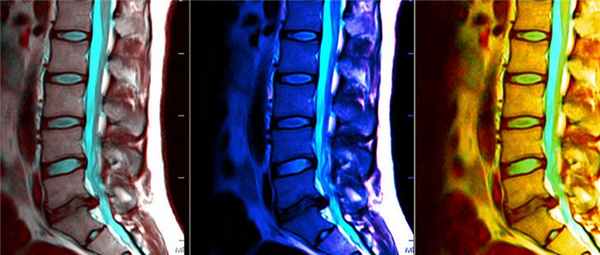

МРТ при миеломенингоцеле

а) Терминология:

• Не покрытый кожей дорзальный дефект позвоночника → нервные образования, ликворные пространства и оболочки спинного мозга контактируют с внешней средой

• Синонимы: менингомиелоцеле (ММЦ), открытая дизрафия позвоночника (ОДП), открытая spina bifida, кистозная spina bifida

б) Визуализация миеломенингоцеле:

• Пояснично-крестцовый отдел (44%) > грудопоясничный (32%) > поясничный (22%) > грудной отдел (2%)

• Предоперационное обследование: не покрытый кожей дорзальный дефект позвоночника → нервные образования, ликворные пространства и оболочки спинного мозга контактируют с внешней средой

• Послеоперационное обследование: дизрафия, низкое расположение спинного мозга/корешков, послеоперационные изменения кожных покровов после выполненной кожной пластики

(Слева) Схема сагиттального вида протрузии оболочек спинного мозга через дизрафический дефект позвоночника, сопровождающийся низким расположением спинного мозга, оканчивающегося невральной плакодой (обозначена красным). На врезке показан аксиальный срез: корешки спинного мозга берут начало от вентральной поверхности плакоды, которая вместе с оболочками мозга пролабирует через дизрафический дефект задних элементов позвонка.

(Справа) MPT, Т1-ВИ, сагиттальная проекция: значительного размера полость миеломенингоцеле пояснично-крестцового отдела позвоночника, пролабирую-щая через дорзальный дизрафический дефект позвоночника. Нервные образования также пролабируют в этот дефект. (Слева) МРТ, Т2-ВИ, сагиттальная проекция: типичные для мальформации Киари 2 изменения задней черепной ямки. Хирургическое лечение по поводу значительных размеров миеломенингоцеле пояснично-крестцового отдела позвоночника в данном случаев не выполнялось.

(Справа) Т1-ВИ, аксиальная проекция: нелеченое миеломенингоцеле пояснично-крестцового отдела позвоночника: большого размера полость вместе с диспластичными нервными образованиями пролабируют через костный дизрафический дефект в задних элементах позвонка.